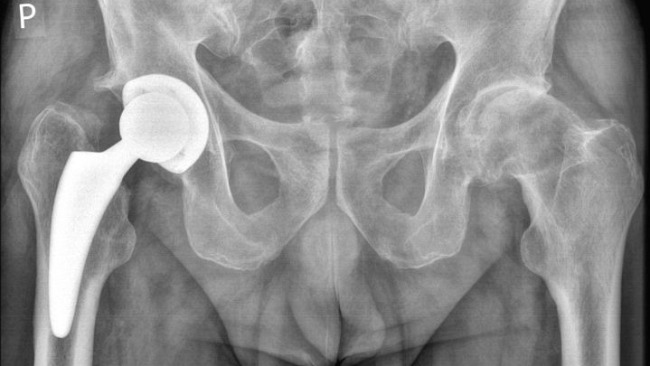

Z powodu choroby ogulnie złego stanu zdrowia jestem po operacji biodra prawego obecnie nie pracuje utrzymuje się ze zwolnienia lekarskiego z krusu i czekam na operację lewego biodrs, Lekarz rodzinny długo leczył mnie proszkami i maściami przeciw bulowymi dopiero prześwietlenie wykazało co mi dolega,Nogę z bulem zaczelem oszczędzać do operacji i naruszyłem drugom nogę która będzie operowana, Wcześniej wyjeżdżałem zagranicę do prac fizycznych jak zdrowie było w porządku, Teraz nie stać mnie na opłaty leki i podstawowe artykuły spożywcze, Posiadam pożyczki jak pracowałem to splacalem na czas przestałem pracować nie miałem na raty pożyczki splacalem biorąc kredyty bankowe i poza bankowe i się zakopałem mam komornika i durze nadzeje jak ludze dobrego serca mi pomogą wyjdę na prostą i wruce do gry, Mam w planach zrobić kurs na Koparko ładowarki żebym miał lżejszy kawałek chleba praca siedzoonca a nie ciężka fizyczna i nie wiem co dalej będzie po operacjach czy wruce do normalnej sprawnośći fizycznej jak byłem wcześniej, Będę zadowolony z karzdej złotówki najważniejsze żeby było na chleb, Bardzo dziękuję daroczyncom ofiarodawcom ludziom dobrej woli i wielkiego serca za każdy datek, Pozdrawiam serdecznie wszystkich ludzi i tych co mają małe i duże serce , PS Rzycie nam czasami kreśli nie samowite zwroty i niespodzianki